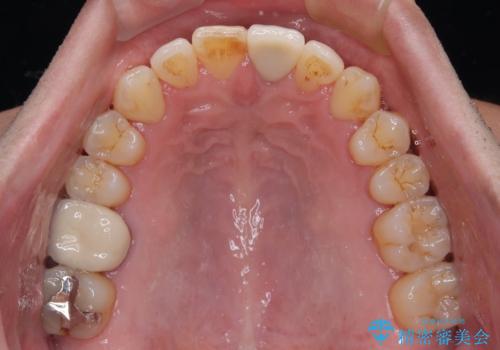

外科処置は希望されなかったので、開咬の改善は限界があると事前にお話ししていたため、上下前歯が完全に接触する前に、もう十分改善したとのことで治療を終了しました。

インビザラインを毎日22時間しっかりと装着してくださったので、我々も驚愕するほどの治療成果が達成されました。